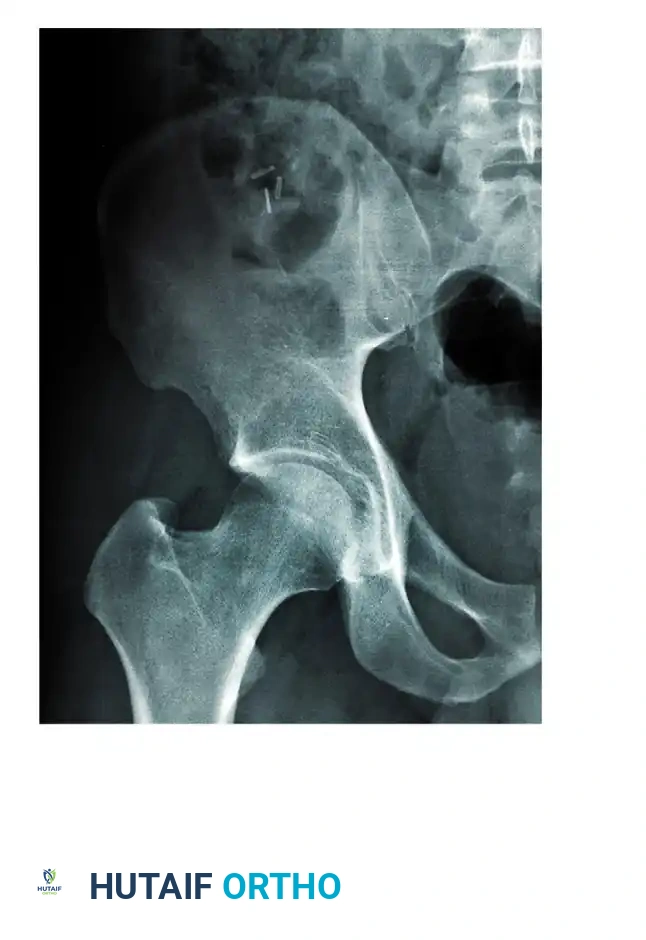

The evaluation begins with an Anteroposterior (AP) view of the pelvis, followed by the two Judet oblique views (Obturator Oblique and Iliac Oblique), taken at 45-degree angles.

Six fundamental radiographic landmarks must be identified on the AP radiograph to understand the fracture pattern:

1. Iliopectineal Line: Represents the anterior column.

2. Ilioischial Line: Represents the posterior column.

3. Radiographic Teardrop: Represents the medial wall of the acetabulum (anterior-inferior portion of the quadrilateral surface).

4. Roof of the Acetabulum: The superior weight-bearing dome.

5. Anterior Lip (Wall) of the Acetabulum.

6. Posterior Lip (Wall) of the Acetabulum.

Fractures traversing the anterior column disrupt the iliopectineal line, whereas posterior column fractures disrupt the ilioischial line.

Computed Tomography (CT):

CT scanning is mandatory. It defines the size of wall fragments, the presence of intra-articular loose bodies, marginal impaction, and the exact orientation of fracture lines. CT is particularly critical in identifying incarcerated fragments that block closed reduction of a dislocated hip.